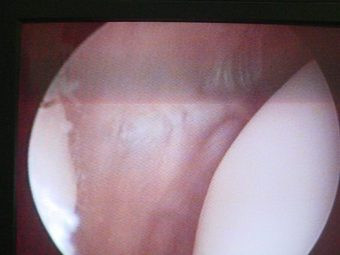

Luxación Habitual de Rótula

Envíado por Dr. Eduardo E. Martínez Melara